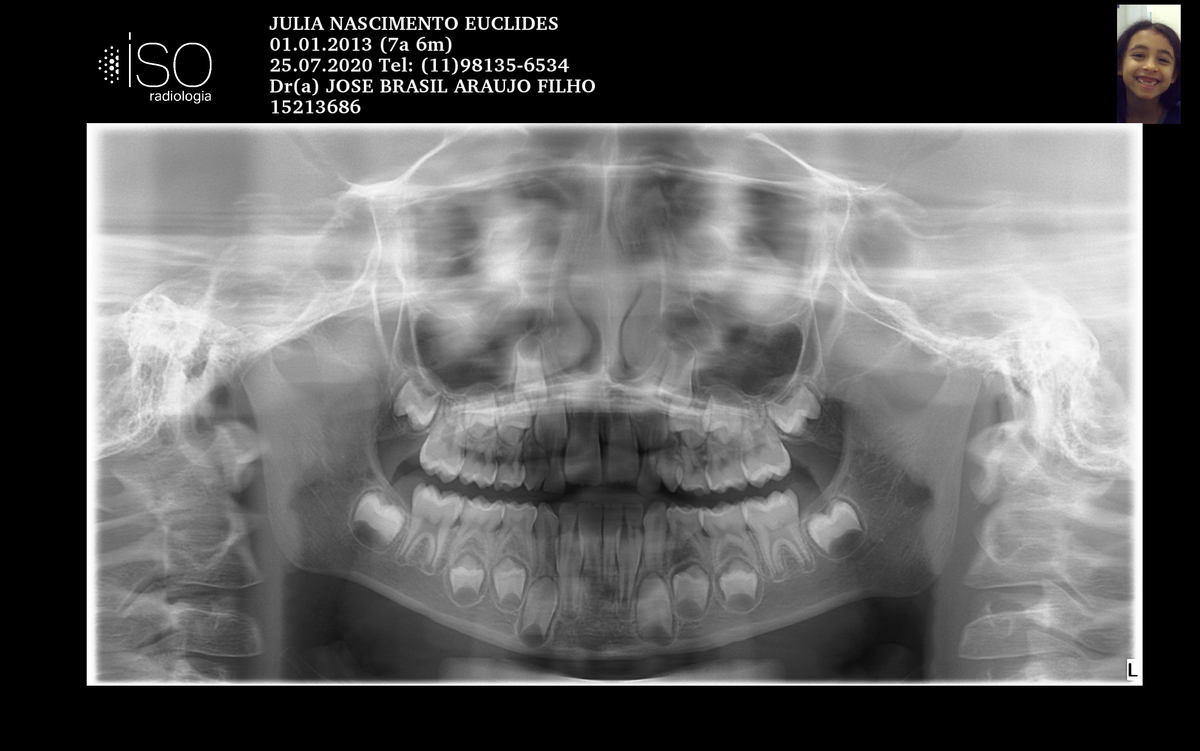

J.N.E.